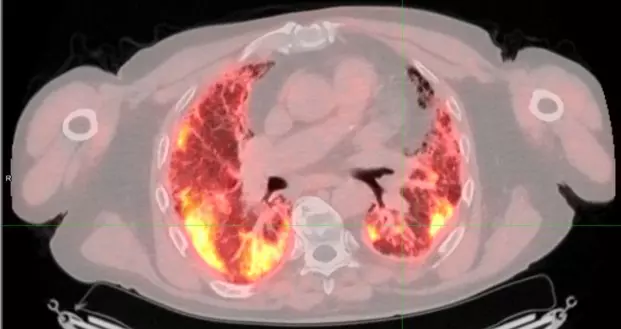

Pour aller plus loin dans la lutte contre cette maladie, le service de Pneumologie de l'Hôpital Erasme a initié une collaboration étroite avec le service de médecine nucléaire (Professeur P. Flamen et le Dr A. Deleu) pour développer un projet novateur d'imagerie moléculaire par PET/CT dans le but de visualiser l'activité de la maladie : le projet FAPI-PET.

​Le principe est d'utiliser un traceur radioactif qui va se lier aux cellules qui fabriquent la fibrose, les fibroblastes. Cette technologie révolutionnaire a déjà fait l'objet d'une première étude prometteuse sur 50 patients, financée grâce aux donateurs du Fonds Erasme. Les résultats, d'ores et déjà présentés lors d'un grand congrès européen de pneumologie et prévus pour une présentation actualisée à Barcelone, sont particulièrement excitants. L'équipe médicale a identifié un seuil (cut-off) du SUVmean : si l'activité mesurée au PET scan dépasse ce seuil, il est possible de prédire avec une sensibilité et une spécificité supérieures à 90 % que la maladie va progresser dans l'année avec un risque significativement plus élevé de décès.

Cette capacité à pronostiquer l'évolution de la fibrose permet d'entrer de plain-pied dans l'ère de la médecine personnalisée. En effet, actuellement, tous les patients reçoivent un traitement standard et on regarde comment la maladie évolue au cours du temps, ce qui fait perdre un temps précieux. Avec le FAPI-PET, le spécialiste peut adapter son approche : face à un patient dont le scan montre une faible activité, le médecin optera pour un suivi sans traitement immédiat ou à faible dose, évitant ainsi des effets secondaires inutiles.

À l'inverse, si l'activité est très agressive, le patient se verra prescrire d'emblée une combinaison de médicaments à dose maximale pour éviter qu'il ne meure étouffé, et ce, même s'il faut accepter des effets secondaires plus lourds tels que la fatigue, la perte d'appétit, la perte de poids ou des diarrhées.